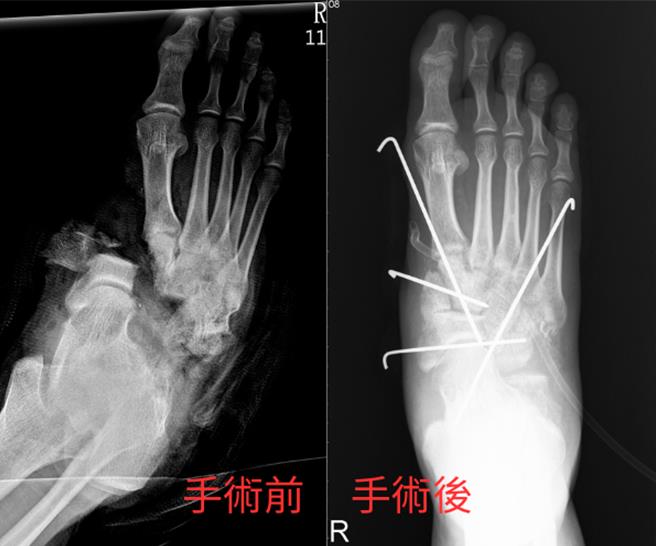

在骨科足踝专科医师王秋猛评估后仍有机会将断肢接回重建,医疗团队把握黄金时机,立即展开马拉松接合手术。为防止细菌感染,医护人员花费长时间清除沾满机油、砂石的伤口后,王秋猛将断骨处以4根骨钉固定,并依序缝补接回肌腱、神经、血管共10余条组织,若对接错误,恐导致组织坏死,手术难度极高。

王秋猛坦言,足踝是下肢重要关节,结构繁复精细,必须对后足解剖构造有十足了解把握才能准确接回断肢。他将断肢大部分接回并缝补后,由整形外科医师林祁岷带领团队接续血管显微手术,过程近9小时;术后3天观察伤口无感染恶化坏死,显见清创确实、断肢重建成功、感染科抗生素组合投药精准。